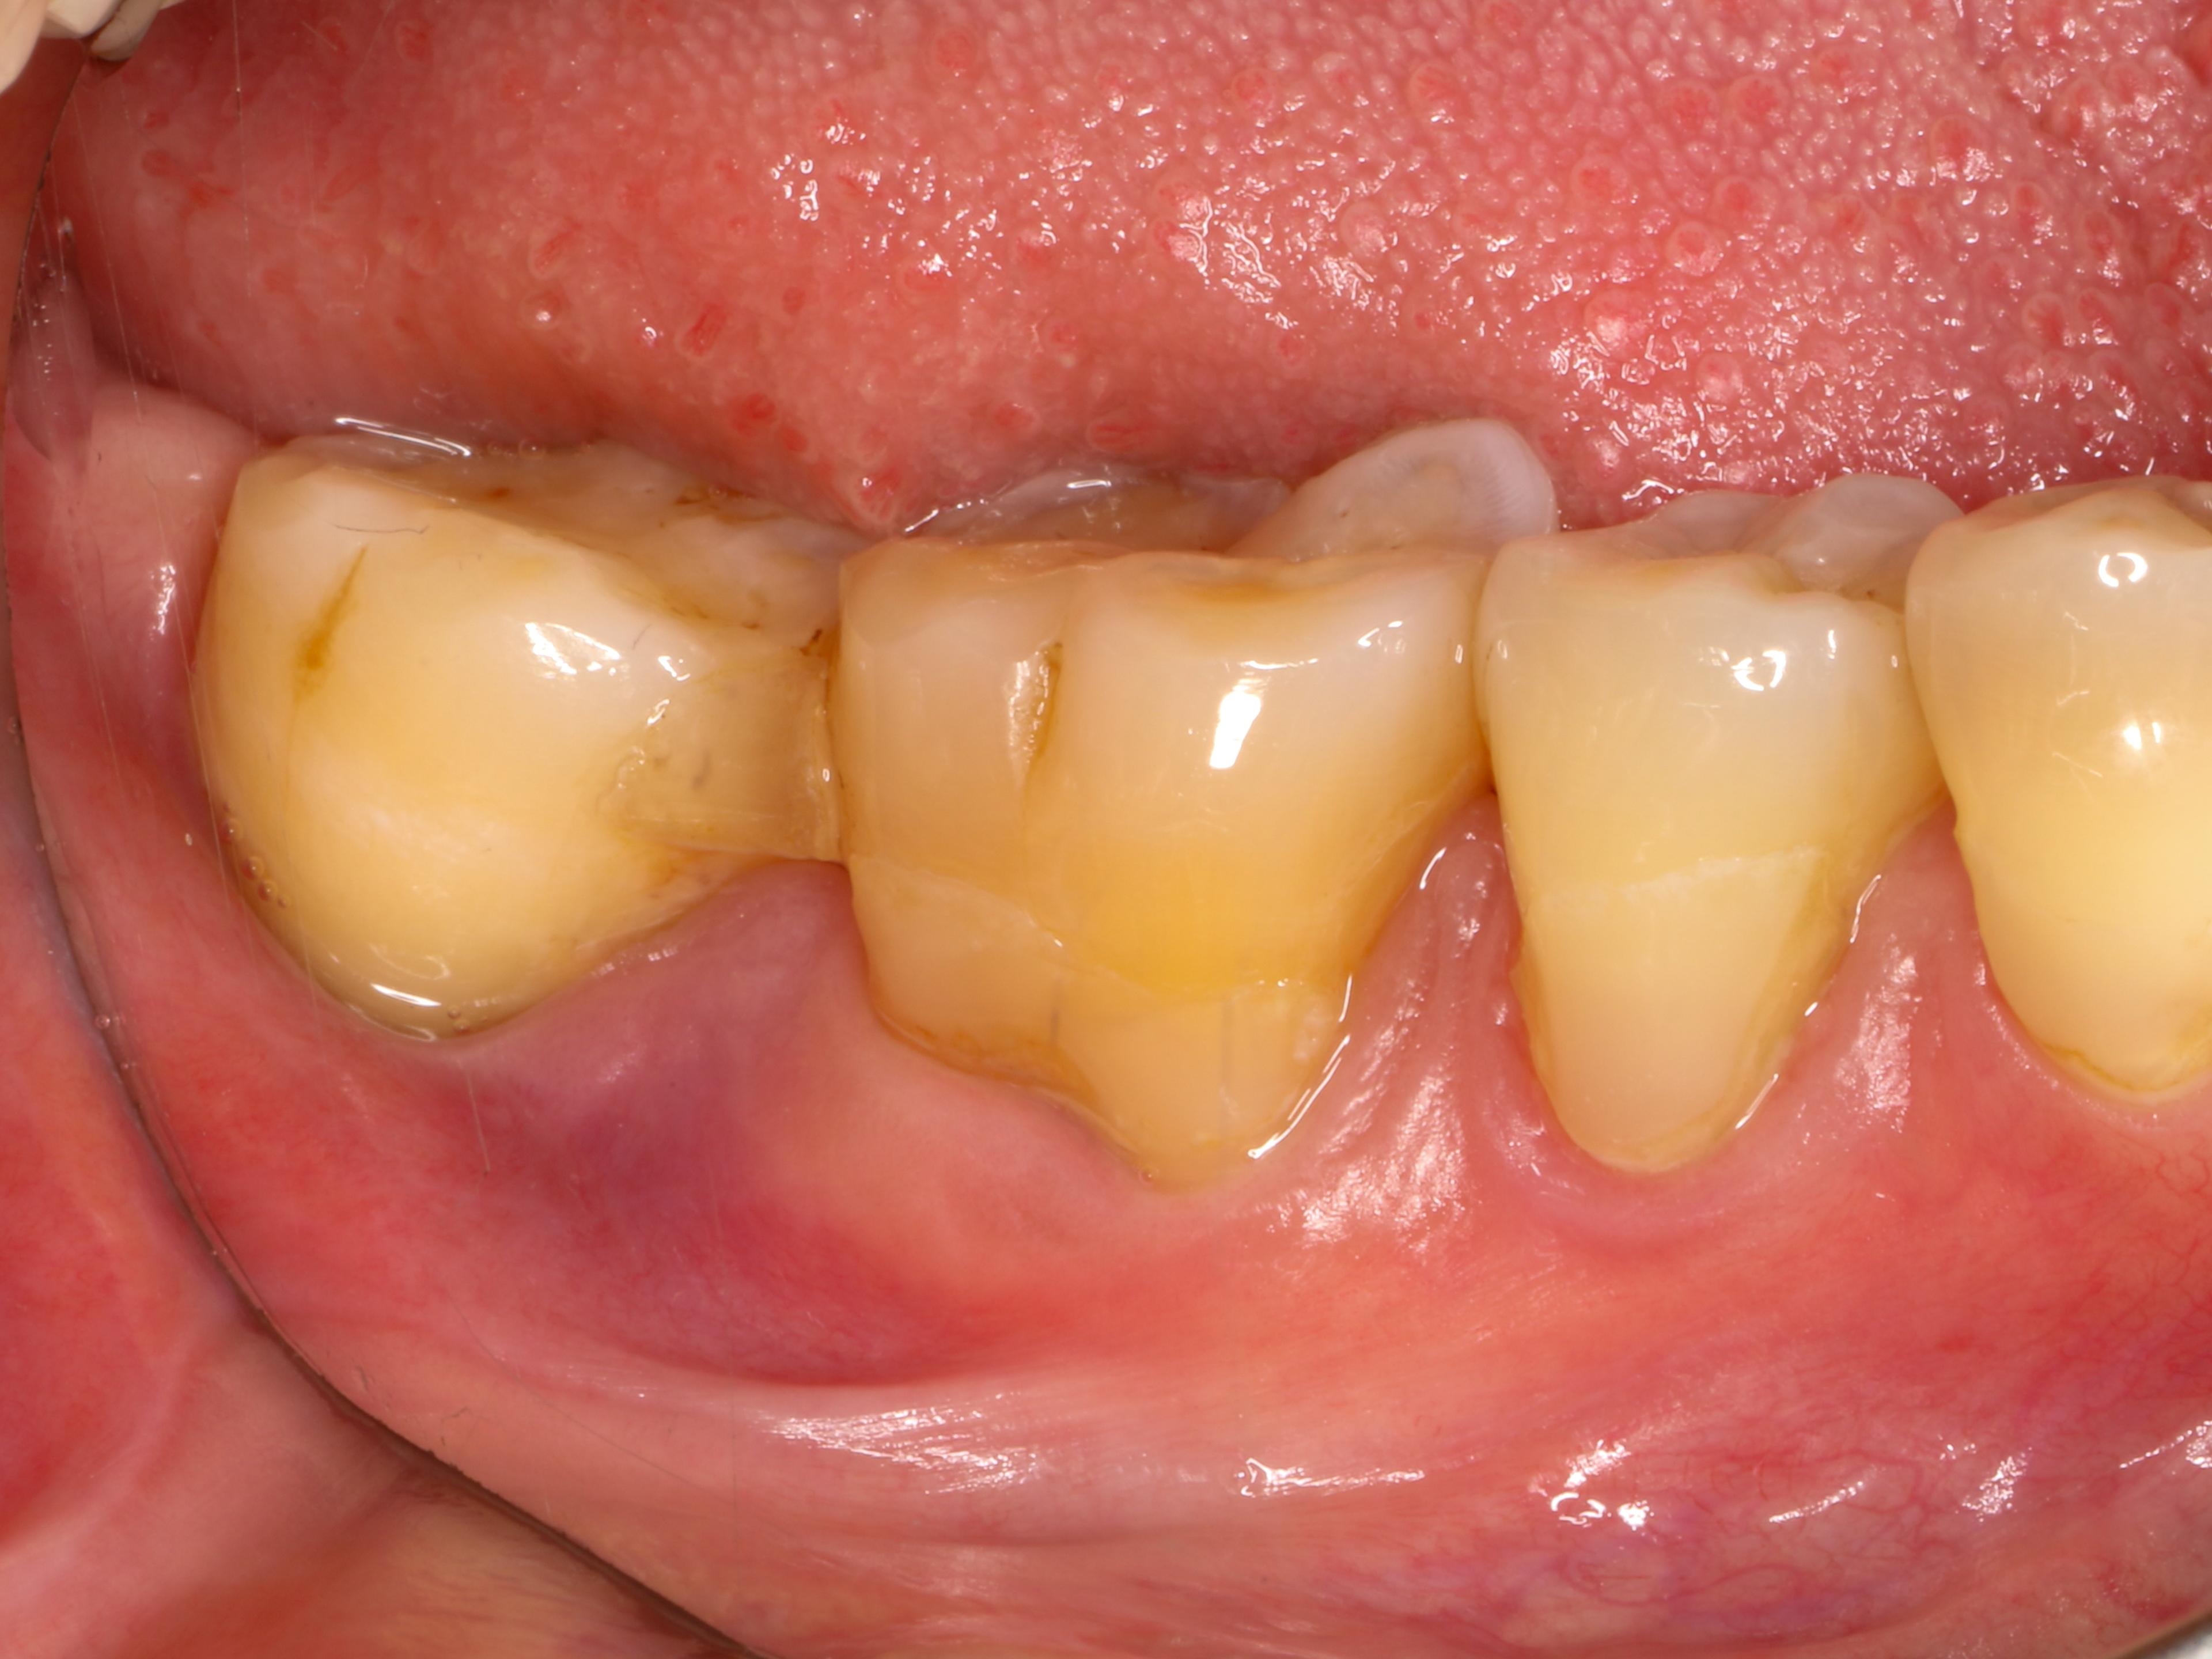

見た目では歯根露出が大きい程度の印象しかない。

広範囲にわたり付着が喪失、舌側中央、遠心のみ付着ありの状態です。噛めないほどにぐらぐらしている状態を想像してください。

歯周基本治療時と再生療法前のプロービング検査の結果です。頬側は全体的に浅くなり近心舌側は10mmから5mmに改善しました。

オペはマイクロスコープ下で行います。フラップ形成後、

歯周基本治療により、歯石はほぼ綺麗に除去されていた

根尖部の歯石様のものは超音波スケーラーで除去。一部セメント質が欠損しており、セメント質剥離を疑いました。剥離しかけのセメント質を除去するよう、ダイヤモンドチップで平坦化を図りました。

デブライドメント後はサイトランスにリグロスを混和したものを設置。歯肉が薄いことから、結合組織移植も行います。